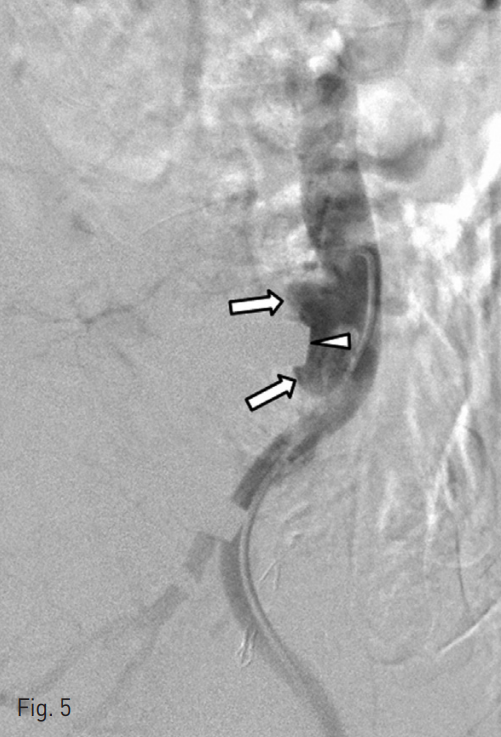

Then, we used N-butyl cyanoacrylate glue (n-BCA, 1 : 3, total 3cc) material to embolize the fistulous tract via microcatheter in left CIA occlusion site pseudoaneurysm (Fig. 4). The postembolization angiogram confirmed the obliteration of the fistulous tract (Fig. 5).

Fig. 5

The lateral aortography after embolization shows pseudoaneurysm-like bulging (arrows) of the distal aorta and the obliteration of the fistulous tract. Note the indentation (arrowhead) of the bulging against the metallic plate